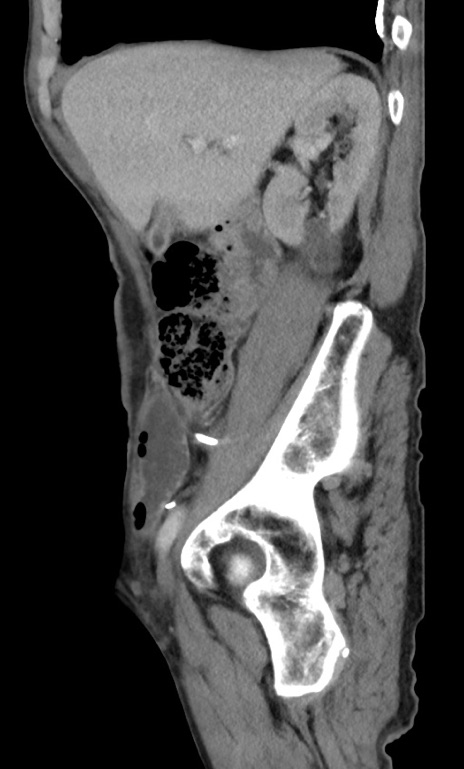

冠状断像